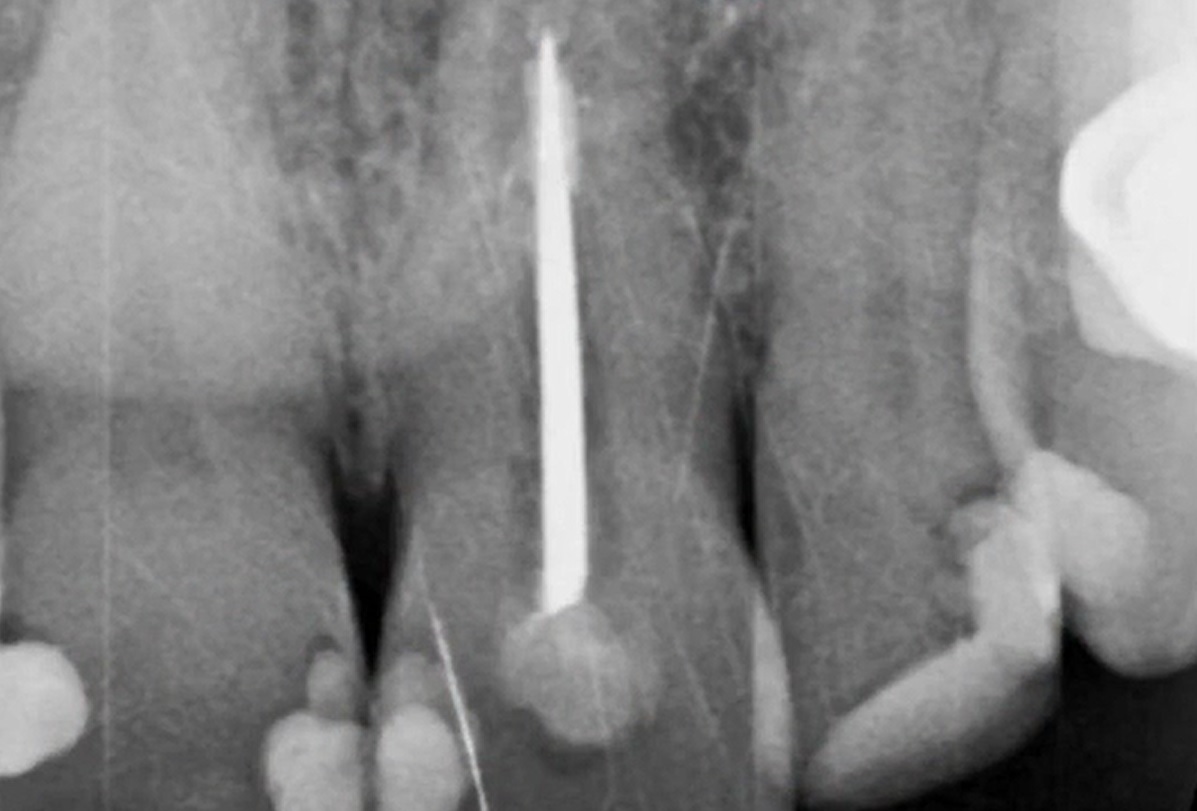

1 6 7 8